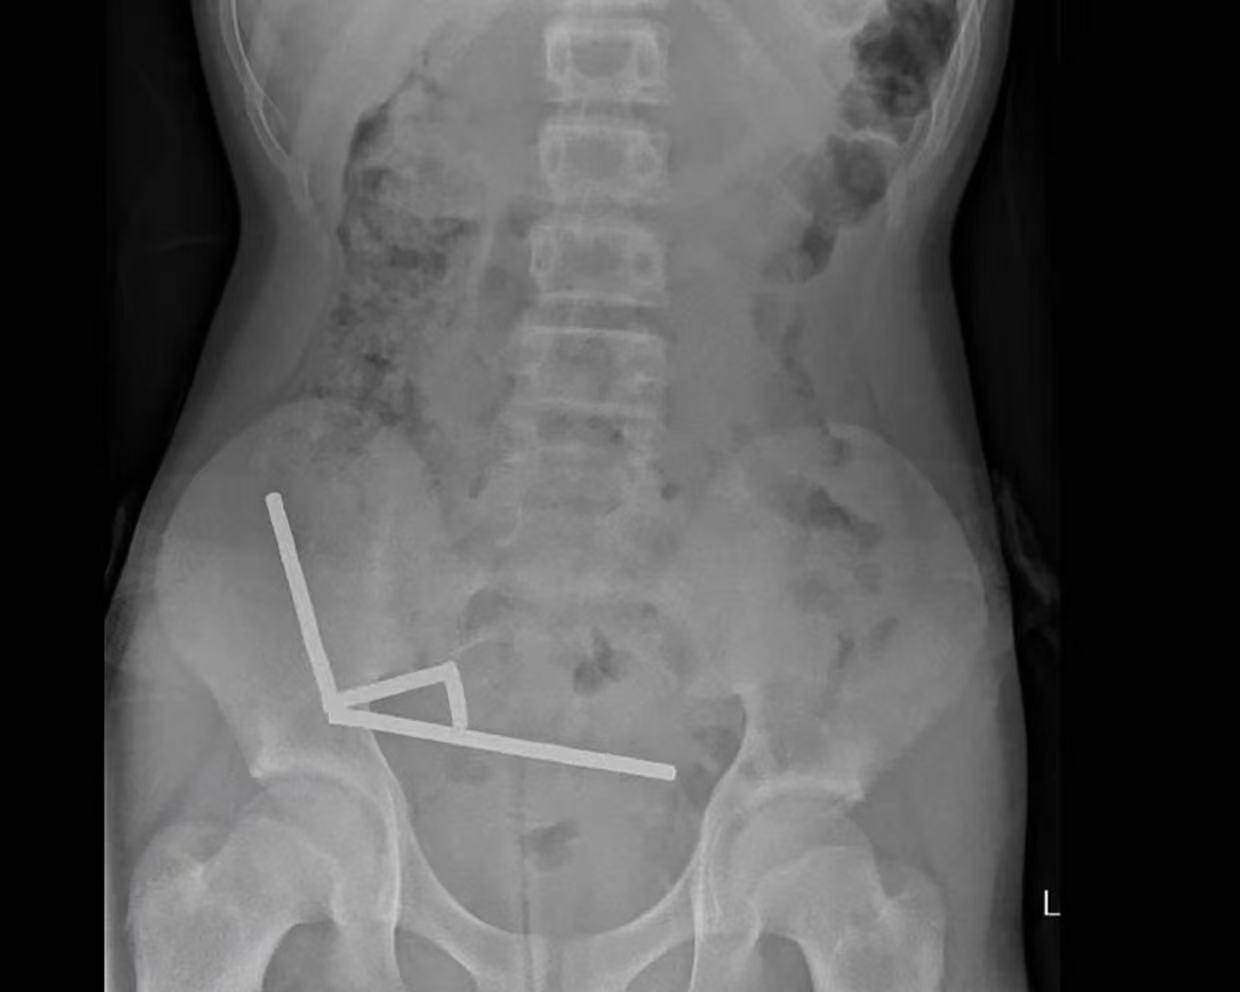

据悉,这名未透露姓名的少年在持续腹痛4天后被送往新西兰北岛的一家医院。医生通过X光检查发现,这些磁铁在他的肠道内互相吸附,形成了四条链状结构。

▲X光显示,磁铁在男孩体内紧密吸附成链状结构

医生介绍,男孩大约一周前吞下了80至100颗大功率钕磁铁,每颗尺寸为5×2毫米。报告称,这些磁铁通过一家跨境电商平台购买。